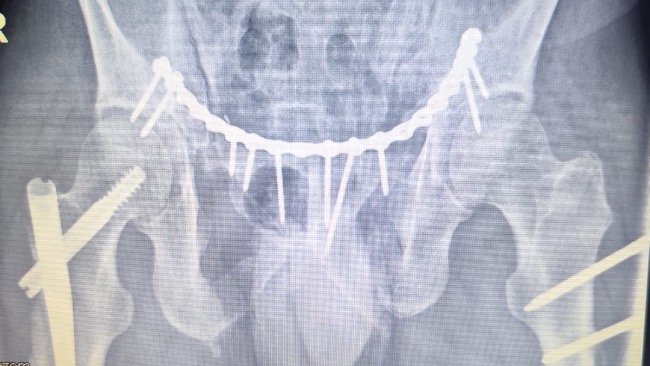

Na miejsce przyleciał śmigłowiec ratunkowy, który zabrał go do szpitala w Olsztynie. Tam rozpoczęła się dramatyczna walka o jego życie. Tata miał zmiażdżone obie nogi, wieloodłamowe złamania obu kości udowych, duży ubytek mięśni i tkanek w lewej nodze, liczne złamania miednicy oraz poważne uszkodzenia narządów wewnętrznych. Lekarze musieli natychmiast operować. Trafił na oddział intensywnej terapii i został wprowadzony w śpiączkę farmakologiczną.

Dopiero po kilku dniach pojawiła się nadzieja i 29 grudnia jego stan się poprawił. Kolejne tygodnie spędził w szpitalu, przechodząc następne operacje i zabiegi. Pojawiły się też powikłania, między innymi zakrzepica, przez którą lekarze musieli wszczepić specjalny filtr przeciwzakrzepowy. Dopiero po opanowaniu stanu zakrzepicy możliwa była operacja stabilizacji miednicy.

Po ponad miesiącu hospitalizacji tata wrócił do domu, ale jego walka wcale się nie skończyła. Do dziś ma w nodze zewnętrzny stabilizator, metalowy stelaż z prętów wychodzących z uda. Nie jest w stanie samodzielnie chodzić ani ustać na nogach. Porusza się na wózku. Przez długie unieruchomienie jego mięśnie bardzo osłabły, a niektóre zanikły.